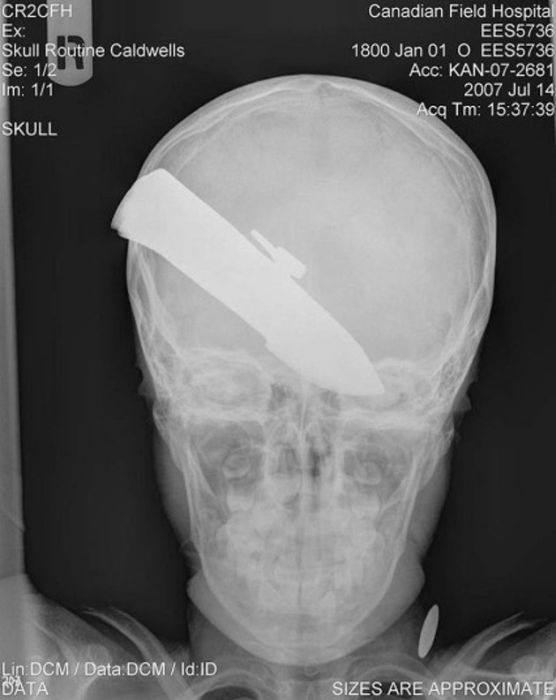

Рентгеновские снимки людей, которые умудрились сами или с чужой помощью разместить внутри своего организма разные посторонние предметы. От вилок и ножей до пуль и бензопилы (!!!). По этическим соображениям обычные снимки таких травм и повреждений выкладывать нельзя, зато рентгеновские можно – на них травмы видны достаточно условно, хоть и очень понятно.